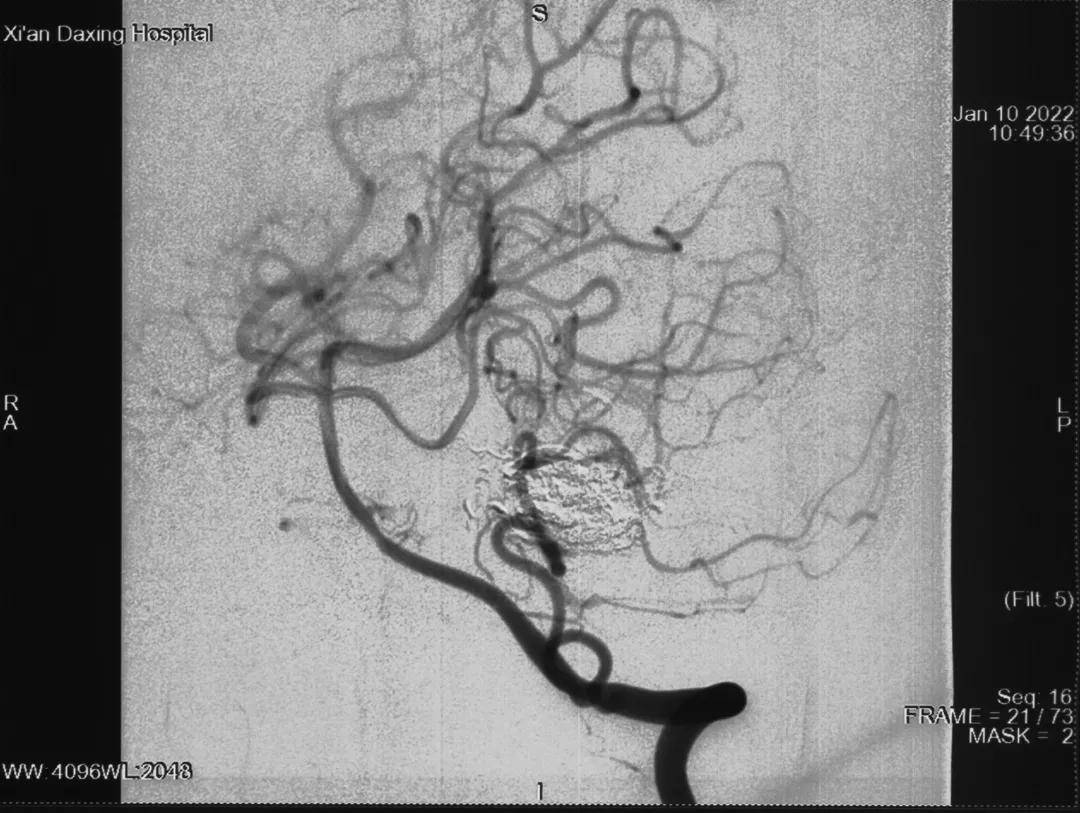

【畸形|当11岁女孩巧遇这对“缠绵恋人” 看神经外科专家如何一招制胜】小吴的脑动静脉畸形位于大脑深部 , 血管路径迂曲细长、畸形构筑不清晰 , 介入栓塞的难度很高;注胶栓塞过程中 , 外科胶又容易误栓邻近的正常血管 , 甚至可能导致症状加重 , 这就对术者提出了更高的要求 , 一点差池 , 就可能会造成不可逆的损伤 。

此外 , 脑动静脉畸形栓塞术还耗时长 , 考虑到患儿的年龄、身体状况、造影剂用量、辐射时间等因素 , 贾栋院长和徐君副主任、曹屹东主任医师等团队其他医生制定了详细的栓塞方案 。

最终 , 小吴在全麻下接受了“全脑血管造影术及动静脉畸形栓塞术” , 成功阻断大部分血管供血 , 有效降低了畸形血管团内的血流速度 。

术中 , 凭借丰富的临床经验和娴熟的手术技巧 , 在神经电生理监测技术下 , 贾栋院长带领徐君副主任 , 使用微导管超选 , 采用液态栓塞系统 , 用导管将液体栓塞剂有控制地注入"大核桃"的供血动脉内 , 使之发生闭塞 , 中断血供 , 降低血流量 , 顺利将畸形血管团栓塞90%以上 , 引流静脉保留良好 , 脑血管得以重新布阵 , 脑血流得到良好的重新分布 。

△术后影像学检查

据贾栋院长介绍 , 动静脉畸形手术难度较大 , 通常情况下 , 栓塞和切除需同时准备 , 双管齐下 。 但是如果能栓塞80%以上 , 可以不做开颅手术 , 而此次手术栓塞达到90%以上 , 取得了相当满意的效果 , 最大程度上保障了患者的生命安全 。